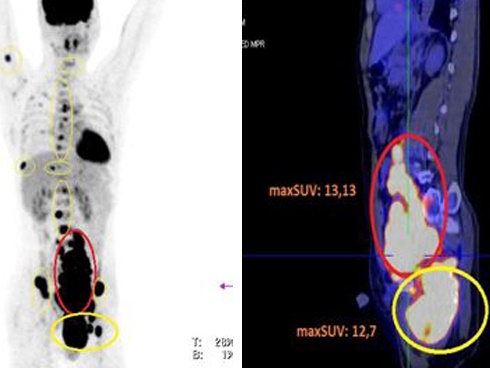

Khi đến BV Ung bướu Hà Nội thăm khám, bác sĩ cho biết, khối u xơ tử cung có kích thước lên tới 25 x 20 cm, tương đương quả bóng.

Ca mổ cho bệnh nhân gặp nhiều khó khăn do u lớn, dính nhiều cơ quan lân cận, nằm chiếm toàn bộ ổ bụng, tăng sinh mạch máu với đường kính mạch máu lên tới 1,2 - 1,5 cm.

“Vì u phát triển đã lâu nên dính quai ruột non, quai đại tràng, dính bàng quang, nếu bóc tách không khéo sẽ làm thủng ruột. Hơn nữa, trong tử cung chứa nhiều thể tích máu gây trở ngại trong việc bộc lộ, thắt mạch tử cung vì khó kiểm soát nguồn nuôi”, TS Kiên thông tin.

Sau hơn 1 giờ, ekip đã bóc tách được quai ruột, cắt hoàn toàn khối u “khổng lồ” có trọng lượng lên tới 3 kg. Đặc biệt, bảo tồn được 2 phần phụ nhằm đảm bảo chất lượng cuộc sống tốt nhất cho bệnh nhân.